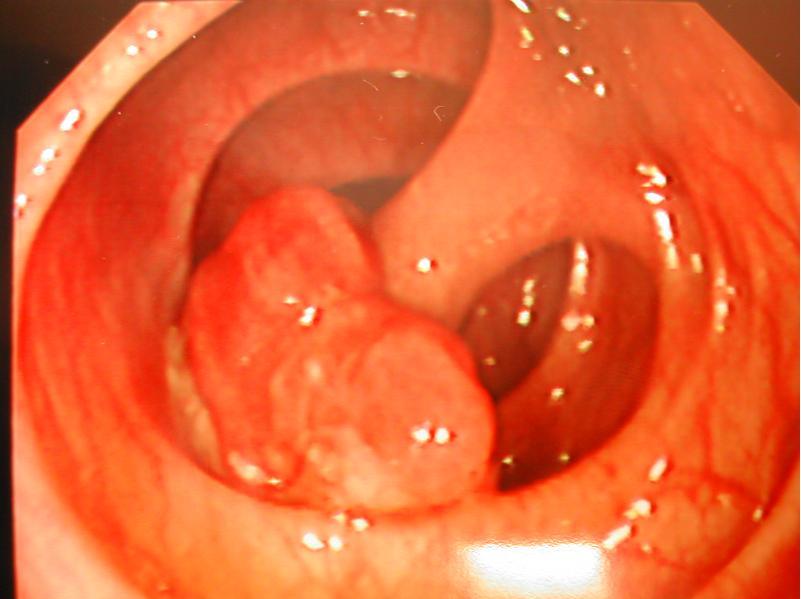

腸息肉有什么癥狀 如何看是不是腸息肉

腸息肉是指患者的腸粘膜表面生長出了一些異常的組織,在還沒有確定這些組織的病理性質(zhì)之前便將它們統(tǒng)統(tǒng)稱為息肉。一般來說,這種疾病對于男性比較多見一些。很多朋友們還不知道腸息肉有什么癥狀,接下來我們就一起來了解一下這種疾病吧!